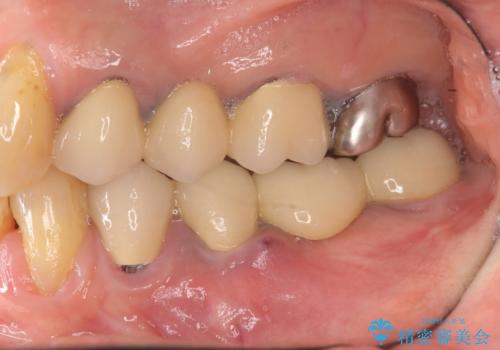

- 以前治療したブリッジが噛むと痛く、食事ができないことの改善を希望され来院されました。

X線写真より、過度な咬合支持負担により支台となる歯の周囲の骨吸収が認められます。今後安定してしっかりとかめるような環境を整備するためにインプラント治療を選択しました。

ブリッジ治療は支台となる歯が弱いと、今回のように周囲の骨が吸収したり歯が割れてしまったりといったトラブルがおきます。咬合力に対抗するため、今回はインプラントを用いて機能回復を行いました。